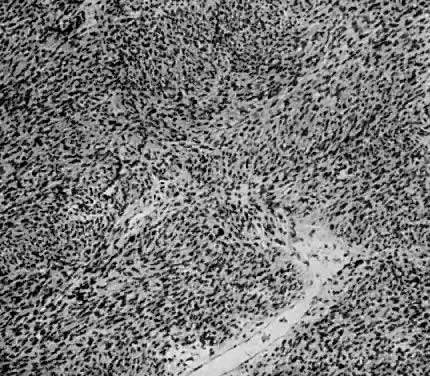

Various terms including mixed mesodermal tumors, mixed müllerian mesenchymal sarcoma and carcinoma, and mesenchymal sarcomas have been used to describe these tumors.5,57,70,70,71,72,73,74,80 These sarcomas contain both stromal and epithelial malignancies and may contain a variety of either malignancy.

The homologous variety contains sarcomatous elements derived from tissue normally present in the uterus. These tumors are commonly referred to as carcinosarcomas (Fig. 14 and Fig. 15).

Fig. 14. Mixed homologous mesodermal sarcoma showing islands of adenocarcinoma ( A) scattered in a leiomyosarcomatous stroma ( B) (H&E, × 350)

Fig. 15. Mixed homologous mesodermal sarcoma composed of islands of adenocarcinoma ( A) and squamous carcinoma ( B) with leiomyosarcoma ( C) (H&E, × 350)

The heterologous variety contains sarcomatous elements derived from tissue foreign to the uterus. These tumors are commonly referred to as mixed mesodermal tumors. The name should include the term heterologous because this is specific (Fig. 16, Fig. 17, and Fig. 18).